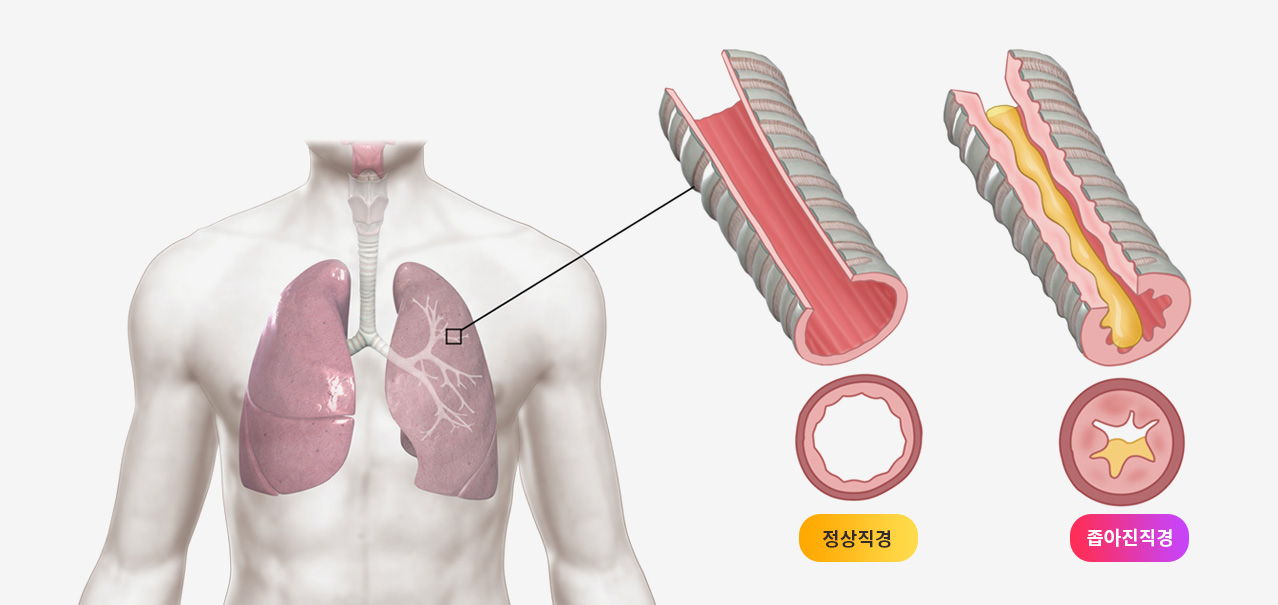

이러한 기침이형천식에 한약치료가 도움이 될 수 있는지 살펴보겠습니다.

그런가 하면 한약이 기침이형천식에 어떤식으로 작용하는지 메커니즘을 설명한 연구도 있습니다.

한약이 기침이형천식치료에 좋은 효과를 내는 메커니즘 연구

기도과민반응 지표인 IL4,IL13를 감소시키고 과민체질인 사람에게 높은 NGF단백질 수치를 내려주고, 천식과 같은 알러지증상에서 주요역할을 담당하는 CGRP 수준을 감소시키는 효과가 있으며 TRP채널을 조절한다.